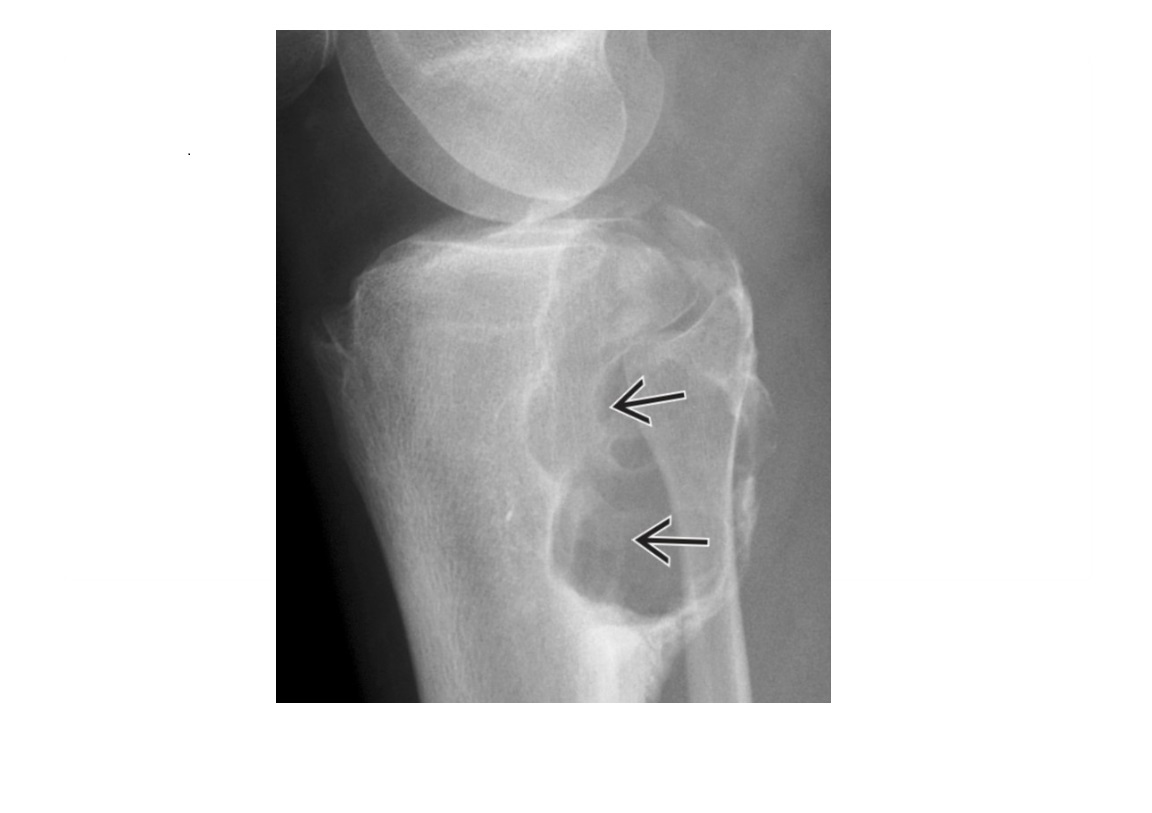

Hyperparathyroidism **'Subperiosteal bone resorption' radial 2nd and 3rd fingers ** **Terminal tuft erosions/resportion = Acro osteolysis ** Brown tumour: -expansile, nonaggressive lytic lesion, Non sclerotic margins -no cortex destruction, periosteal reaction, soft tissue mass or matrix Superior and inferior rib notching Rugger jersey spine/osteosclerosis is associated with secondary hyperparathyroidism chondrocalcinosis salt and pepper skull -due to generalized bone resorption with more focal areas of lucency ± patchy sclerosis 1° hyperparathyroidism (HPTH): parathyroid adenoma (75-85%) Tc-99m sestamibi scan and US for diagnosis 2° HPTH: chronic kidney disease most common Nb Renal osetodystrophy is 2° HPTH and oestomalacia